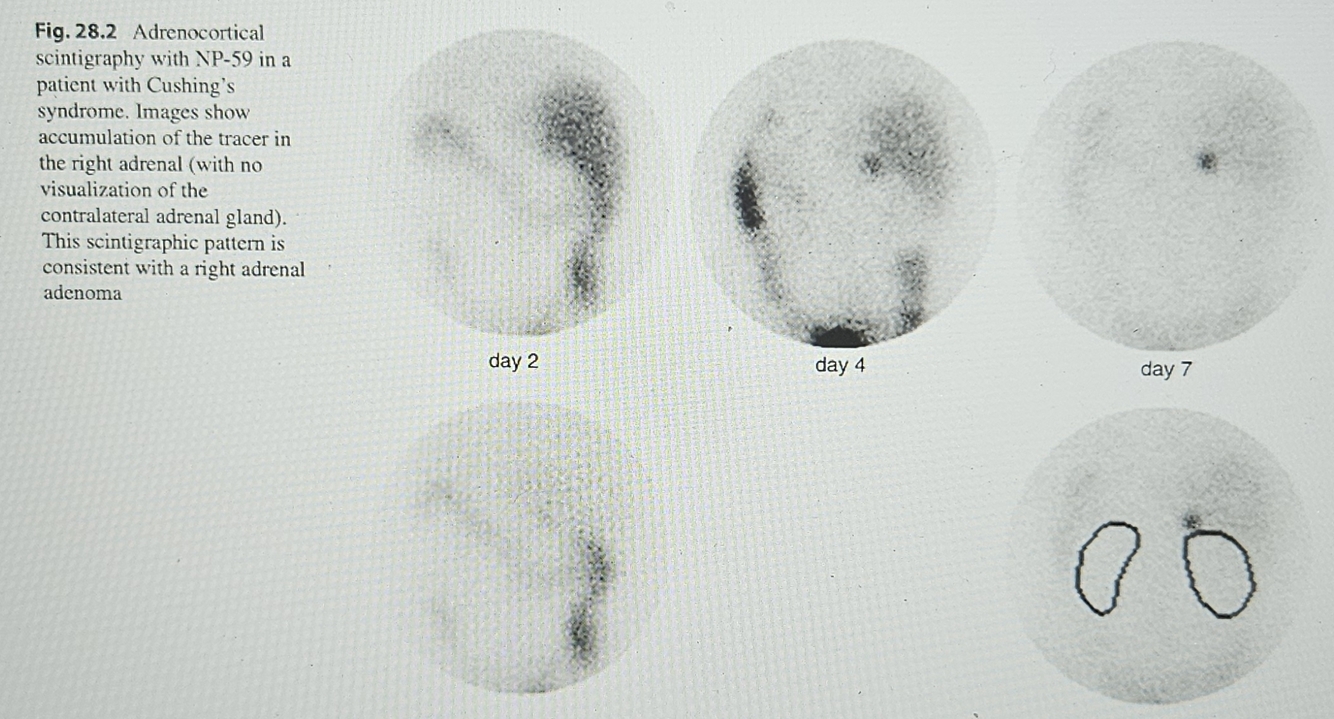

Hypercortisolism (fascicular zone) - - image of cortex by NP-59

Cortisol hypersecreting adenoma - - monolateral uptake, contralateral not visualized, ACTH independent

NP-59 Right adenoma

Monolateral uptake, contralateral not visualized

Primary adrenal adenoma ACTH independent